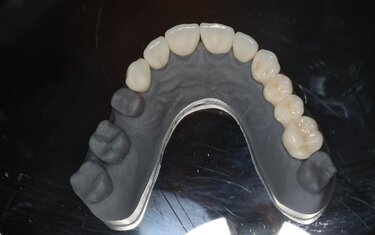

Figure 10: From the scan of the final design, a model was 3D printed

and a putty wash matrix used to create temporaries.

Figures 12: The final milled restorations on the model and seated in the mouth.

Figures 13: The final milled restorations on the model and seated in the mouth.